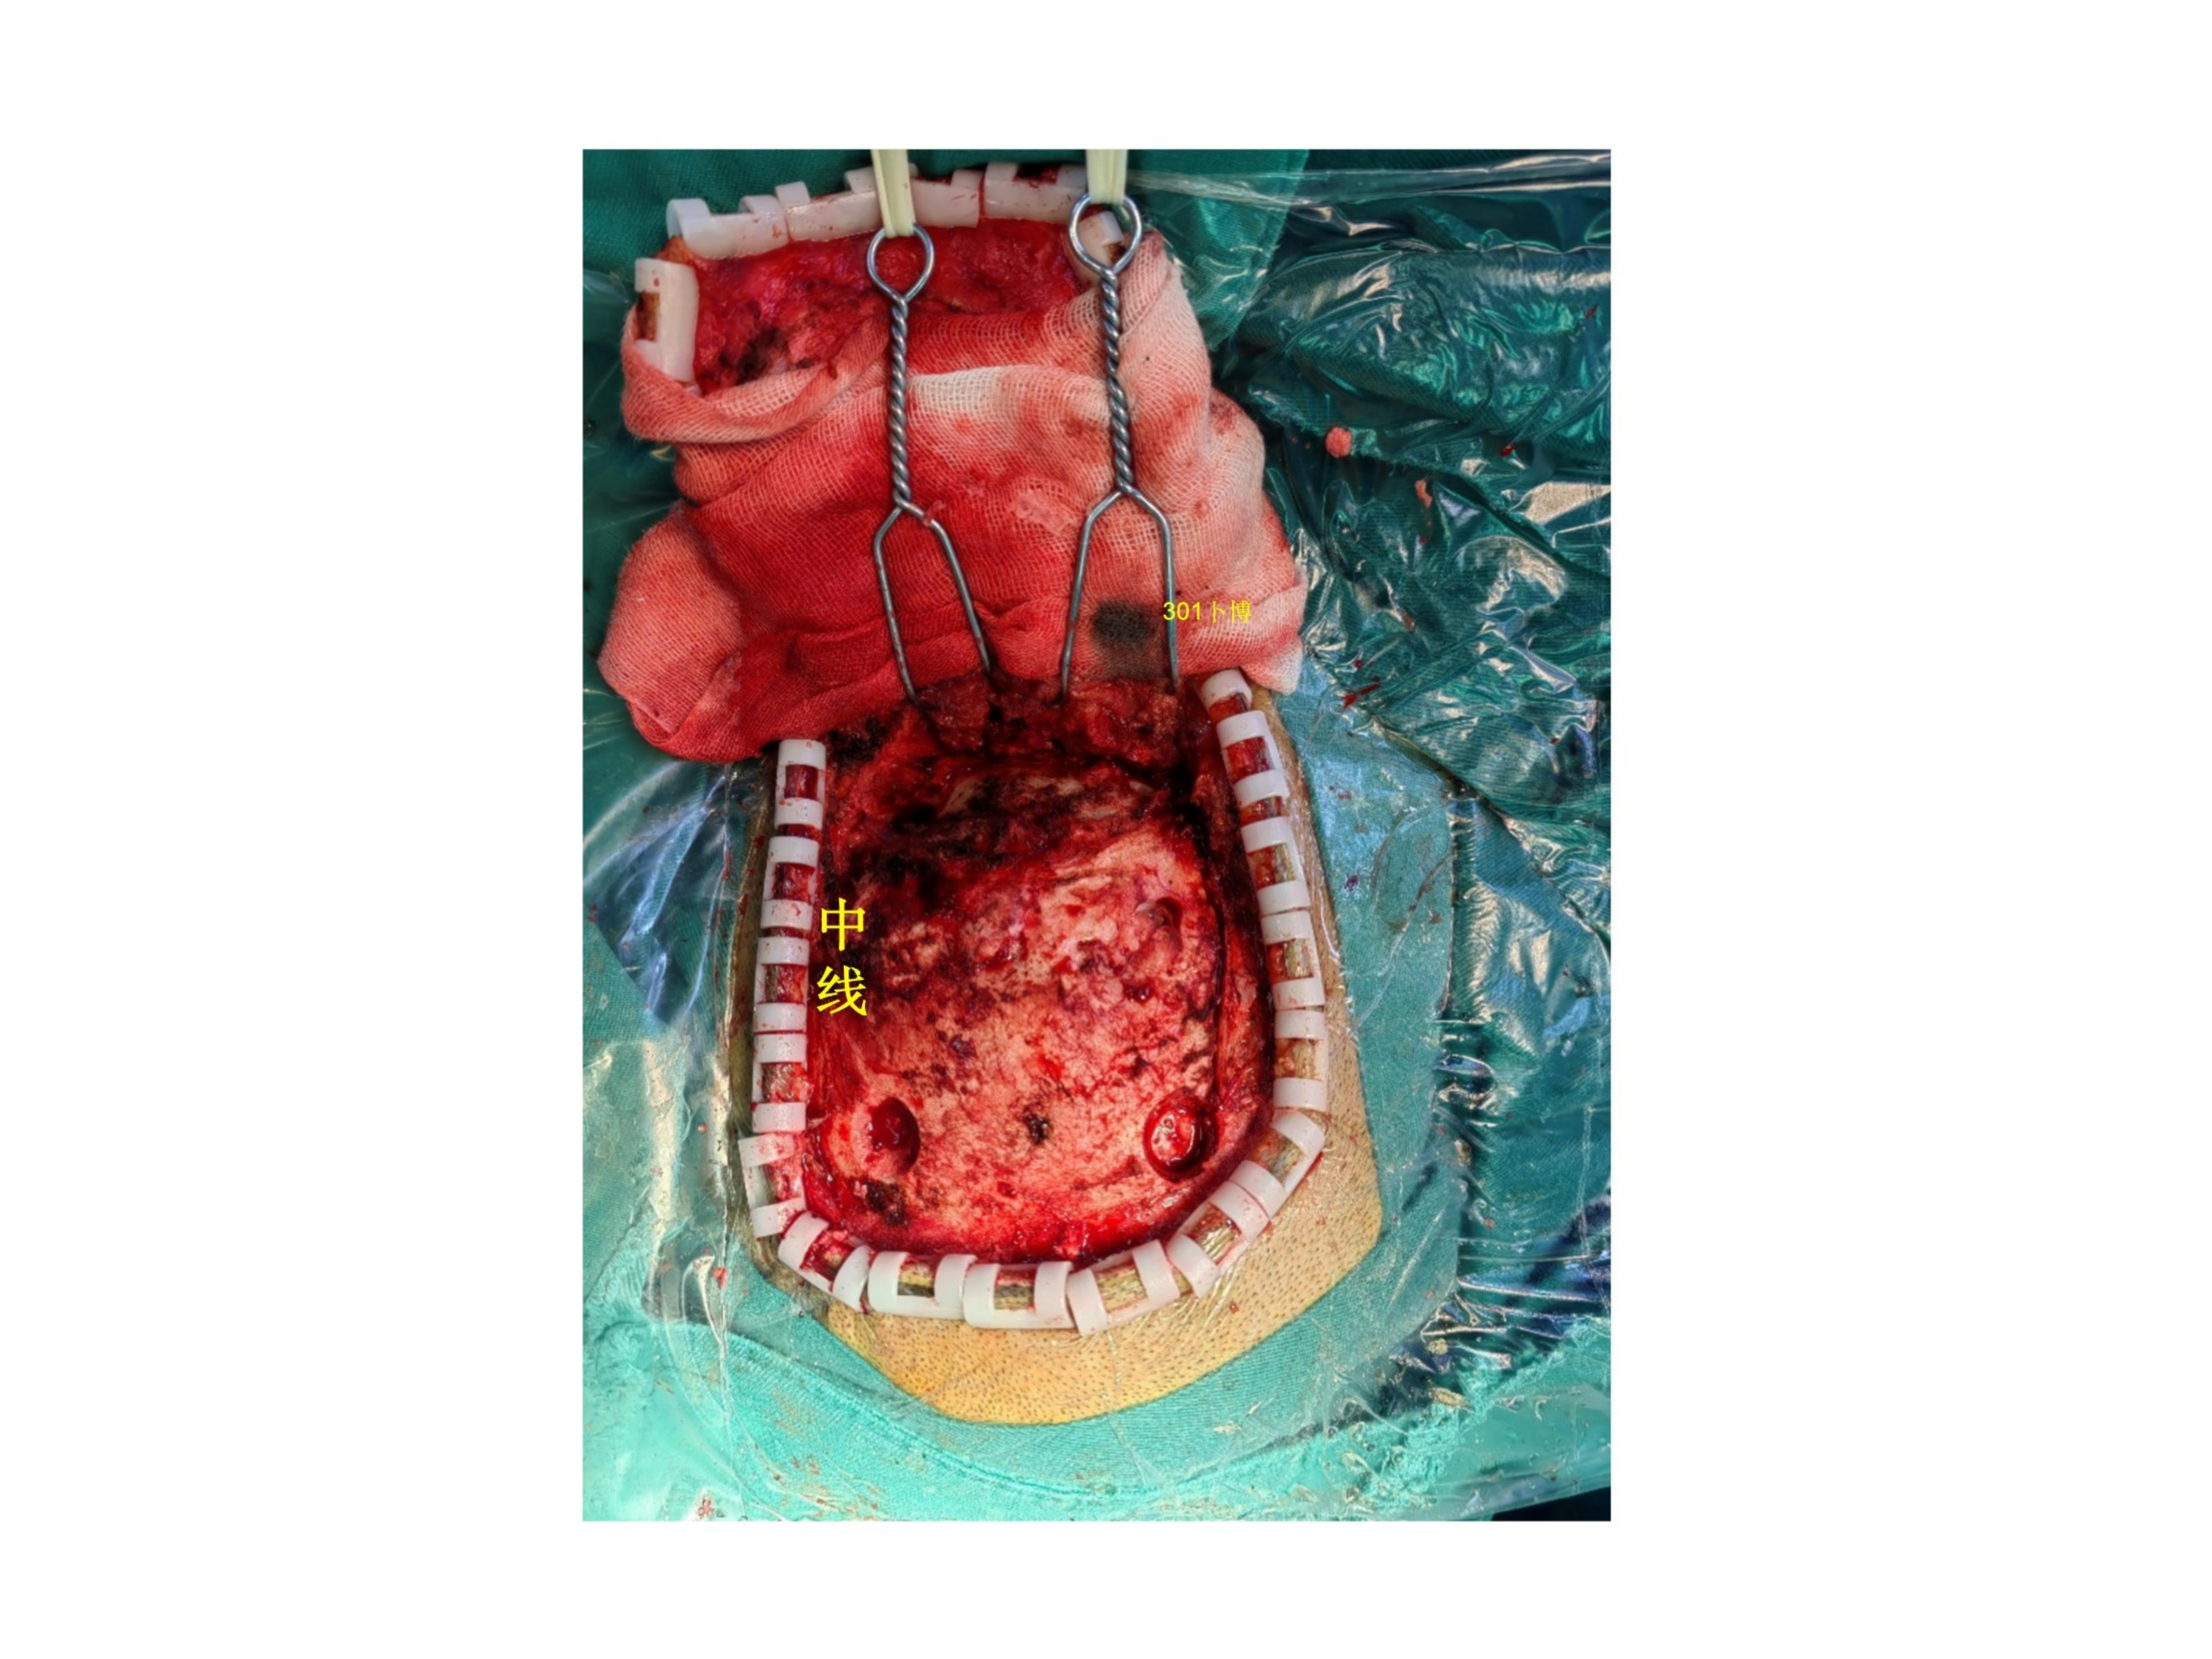

患者主要表现为双眼视力下降一个月余,加重3周。患者1个月前无明显诱因出现双眼视力下降伴视物重影,就诊当地医院行眼科相关检查,未能发现病因。3周前患者因头晕就诊徐州市中心医院,行头部CT提示颅内占位,进一步行头部磁共振检查提示脑膜瘤可能,建议手术治疗。1周前来我院就诊。查体:视力双眼0.6,右侧颞侧同向偏盲。眼底视乳头水肿。余神经系统查体阴性。诊断考虑为小脑幕-横窦-窦汇区脑膜瘤(侵袭性、WHO级,或者孤立纤维瘤)。手术前行栓塞两次,栓掉了大部分血供,同时看到左侧横窦闭塞,窦汇区通畅,静脉引流至对侧。手术采用俯卧位,导航下确认上矢状窦和窦汇区的位置。横窦已闭塞。中线旁跨横窦骨瓣。骨瓣已被肿瘤穿透。以上矢状窦后部为中心,星状剪开硬膜。抬起枕叶切除肿瘤以及受累及的横窦(已闭)小脑幕,向前(术野深面)切除至正常小脑幕边缘,幕间窦发达,一一电凝之。外侧结扎横窦乙状窦移行处,局部取枕部肌肉缝合加固,注意保护labbe静脉汇入点。向内导航下确认窦汇区的边缘。局部结构混乱,窦壁、大脑镰和小脑幕不通程度受累,正常窦壁侵犯无法准确辨认,只能导航确认一下边界。而且肿瘤充分切除减压以后局部膨隆,随呼吸节律波动,考虑窦壁菲薄。理想状态是切除受累及的窦壁并修补(见手绘文献图片)。考虑其为全脑静脉血管的最主要回流通道,没有准备好血管分流管,故未进一步切除受侵犯的窦壁。肿瘤次全切除。病理报告为孤立纤维瘤。术后三个月MRI增强提示切除理想,窦壁略增厚。建议补充伽马刀治疗。